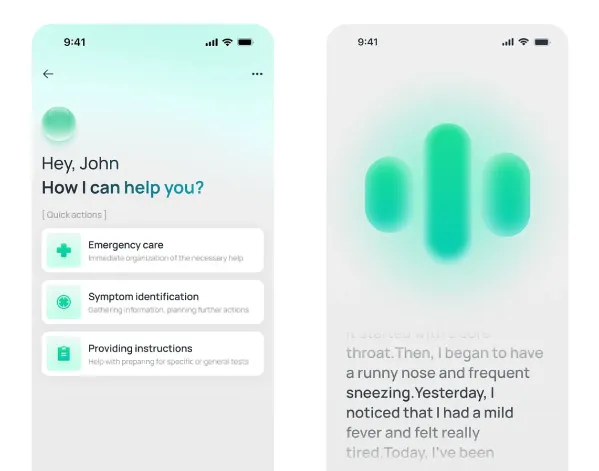

Discover Next-Gen Healthcare Management – Watch Live

Smarter Healthcare Solutions for Modern Patients

Simplifying Doctor Appointments and Healthcare Access

Virtual Healthcare Consultations Anytime, Anywhere

Intelligent Digital Assistant for Healthcare Needs